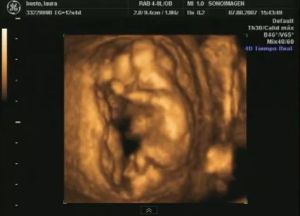

13 semanas

Si un feto de 13 semanas no es un ser humano,no te preocupes

que No Estas Embarazada.